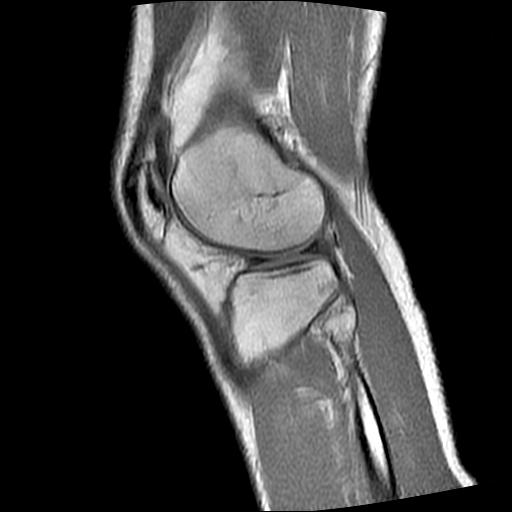

标题: MRI1265:男性40岁,右膝关节 [打印本页]

标题: MRI1265:男性40岁,右膝关节

40岁男性,右膝关节外伤,x光平片示,髁间隆突撕脱骨折。

1、前交叉韧带撕裂;

2、外侧半月板后角撕裂;

3、关节腔积液。

前交叉韧带撕裂,关节腔积液.

半月板1-2级损伤   前交叉韧带撕裂伤   关节腔少量积液  诸骨未见新鲜外伤性改变

髁间隆突撕脱骨折;内侧副韧带损伤。

内侧副韧带撕裂及关节腔积液是肯定的,但是前交叉撕裂确定吗?会不会有容积效应的因素,因为前一张前交叉显示清楚,连续性良好,且较光滑。请问楼主有关节镜支持吗?我们医院也经常有这样的患者,但苦于没有关节镜,而无法对照、证实(除非完全断裂),出现了不同的诊断结果只能毫无意义的争论。

1、前交叉韧、内侧副韧带撕裂;

3、关节腔积液。4、髁间脊撕脱骨折。

除了关节积液外并无韧带撕裂,acl胫侧附着点有2束,正常情况下脂肪信号。此病例应加做压脂像以便观察是否有骨损伤。